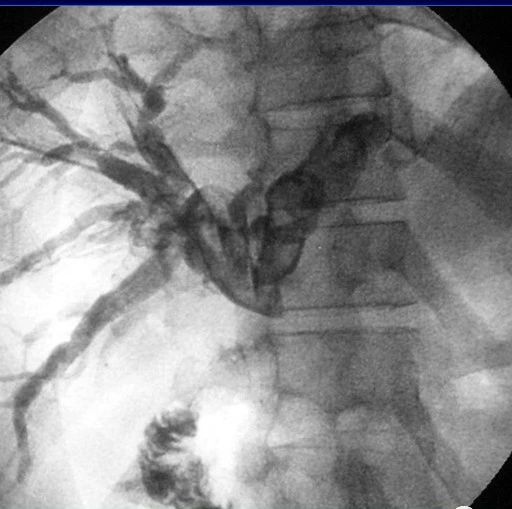

Caroli病鉴别诊断

Caroli疾病影像表现